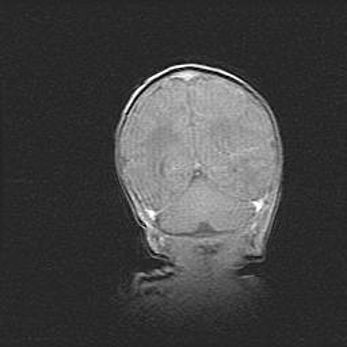

Наружная гидроцефалия с возможной атрофией височных областей.

Возраст: 28 дней

Вес: 3670 г

Пол: мужской

Окружность головы: 38 см

Срок гестации: 40 недель

Гидроцефалия головного мозга у новорожденных – это заболевание, которое характеризуется скоплением избыточного количества спинномозговой жидкости в желудочковой системе головного мозга в результате затруднения её перемещения от места выработки к месту поглощения в кровеносную систему или вследствие нарушения абсорбции. При открытой наружной форме гидроцефалии у новорожденных расширяются и переполняются субарахноидные пространства.

При нормотензивных  формах,  которые,  как  правило,  являются  следствием  перенесенных ишемических  повреждений  паренхимы  мозга,  возможно  сочетание микроцефалии  с нормотензивной гидроцефалией. В основе данных изменений лежит атрофия больших полушарий с преимущественной  локализацией  в  лобно-височных  областях.